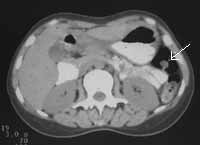

Рис. 3. Рак поперечноободочной кишки: локальное утолщение задней стенки кишки вблизи печеночного изгиба (стрелки), наличие увеличенных до 1,1 см лимфоузлов вблизи измененной кишки.

Рис. 4. Рак восходящей кишки: неравномерное утолщение стенок (стрелки) с инфильтрацией переднего листка околопочечной фасции и околопочечной клетчатки.